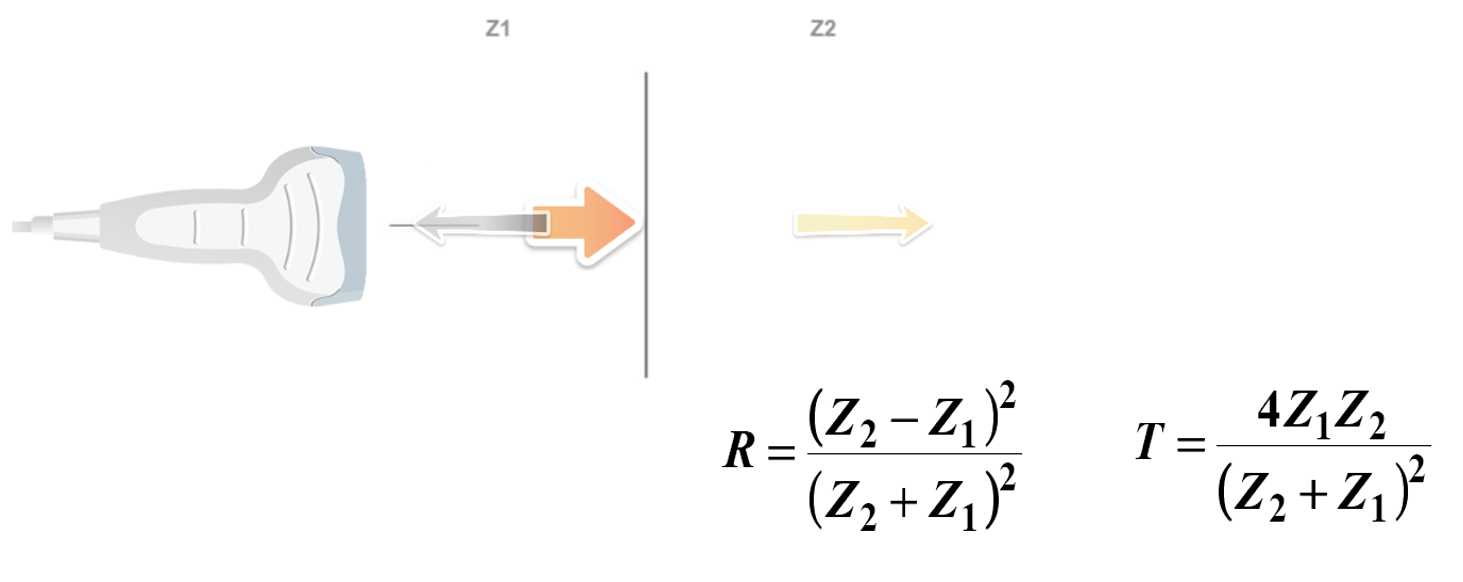

Reflection / Transmission

The Reflection of a sound wave occurs when the wave passes between two tissues of different acoustic speeds and a fraction of the wave ‘bounces’ back. Sound waves that are reflected directly to the transducer will lead to the vibration of the crystals, thus causing an electrical signal and creating the desired image. The equations of transmission and reflection of the ultrasonic intensity are independent of the frequency. Therefore, changing the transducer frequency does not change the transmitted or reflected intensity fraction at an interface. The three beams have the same direction.

Acoustic Impedance

The acoustic impedance is a physical property of biological tissues. It describes the resistance that an ultrasound wave encounters as it passes through a tissue. It is important to know that the discontinuities in the acoustic impedance are responsible for the echoes on which the ultrasound imaging is based. The higher the difference in impedance, the greater the amount of reflection. The acoustic impedance depends on the density of the tissue(ρ in kg/m3) and the speed of the sound wave-wave (V in m/s); if the density of tissue increases, impedance increases. Similarly, if the speed of sound increases, then impedance also increases. Z = ρV

The bones have a high degree of reflection because their acoustic impedance is extremely high (7.8) compared to other tissues of the body. The air has a high degree of reflection because its acoustic impedance is extremely low (0.0004) compared to other tissues of the body. For this reason, it is important to apply a good quantity of conductive gel (a medium of acoustic coupling) on the transducer surface to eliminate any air pockets between the transducer and the skin surface.

Otherwise, most of the ultrasound waves will be reflected, limiting the penetration into the tissue. Highly dense tissues, such as bone or kidney stones, easily reflect echoes, and therefore, appear in white on an ultrasound image. Also, as in the intestine, the air reflects the echoes easily, so that the edge of the intestine appears in white on an ultrasound image. Thus, substances whose density differs significantly may appear in white on an ultrasound image. The acoustic properties of soft tissues are very similar to those of water. However, the acoustic property of the air is distinctly different; thus, the presence of air between the probe and the tissue of interest can deform and obscure the image. For this reason, a density of water, called coupling means, is used for the transmission of the ultrasound image. This coupling means is usually a sonographic jelly or lubricant that should be placed between the probe and the skin surface. At an air-tissue interface, 99% of the beam is reflected, and therefore, the application of this gel is highly important.

The greater the difference in acoustic impedance between two adjacent tissues, the more ultrasound energy will be reflected at the boundary. The acoustic shadow occurs when the sound wave meets a very dense structure. Almost all the sound is reflected, resulting in an acoustic shadow. Shading can occur due to intense reflectors such as calcification, air, or bone.